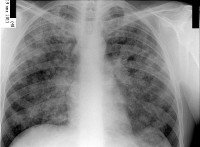

Острый диссеминированный туберкулез легких чаще всего имеет гематогенное распространение. По размеру туберкулезных очагов он делится на мелкоочаговый (милиарный, с очагами диаметром 1-2 мм) и крупноочаговый (очаги диаметром до 10 мм). При милиарном туберкулезе на рентгенограммах выявляется густая «просовидная» диссеминация, обычно расположенная симметрично в обоих легких. Может протекать по тифоидному (с лихорадкой и резкой интоксикацией), легочному (с выраженной дыхательной недостаточностью) или менингеальному варианту (с явлениями менингита, менингоэнцефалита). Острый крупноочаговый туберкулез легких протекает в виде долевой казеозной пневмонии; очаги крупные, симметричные, с преимущественной субплевральной локализацией в верхних долях. Прогрессирование крупноочаговых изменений может приводить к деструкции легочной ткани с формированием каверн.

Рентгеносемиотика диссеминированного туберкулеза легких зависит от клинической формы заболевания. Признаками острого процесса служат наличие в обоих легочных полях множественных однотипных очагов, расположенных симметрично, в виде цепочки по ходу сосудов. При подострой диссеминации очаги имеют тенденцию к слиянию, возможно образование полостей распада. Для хронической диссеминации характерно асимметричное расположение очаговых теней, которые имеют разную форму, величину, очертания, интенсивность в зависимости от срока давности их возникновения. Рентгенография легких, как правило, дополняется линейной или компьютерной томографией.